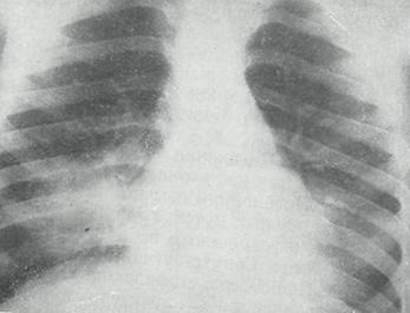

Острая внебольничная пневмония по МКБ-10: признаки и примеры